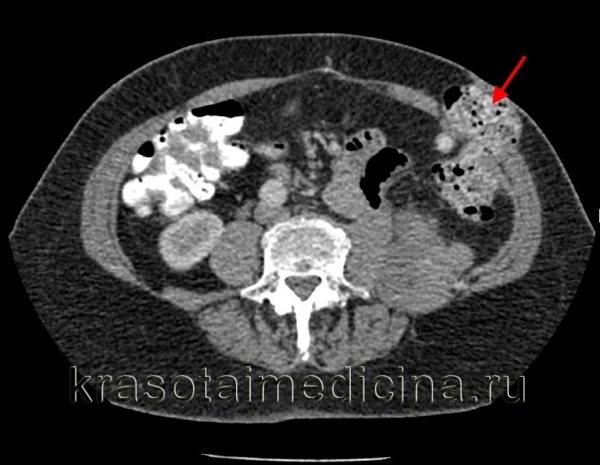

КТ ОБП. Пролабирование петли нисходящей ободочной кишки через боковую стенку живота в подкожную клетчатку.